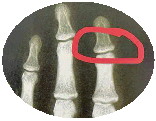

李宁向记者讲述骨缝与生长的关系。

有生长空间的骨缝。

无生长空间的骨缝。

当然,如果想看看孩子的生长发育水平,可定期给孩子测骨龄,即左手或手腕的x光检查,“骨龄的检测建议每半年或一年进行一次”。

李宁说,骨龄是骨骼的年龄,和身高增长密切相关,定期测量有助于预测孩子的生长空间。